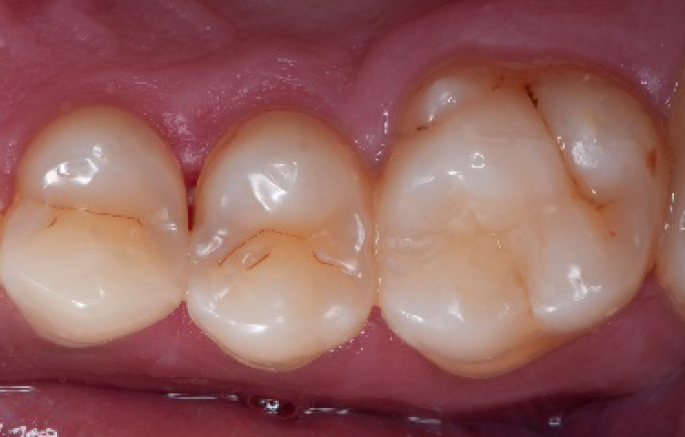

Initial situation of the patient

The patient came for a routine control appointment. She didn‘t report any symptoms but some bleeding during brushing.

Initial situation: an old class I composite restoration on 1.6. New caries on the mesial wall. Presence of plaque and inflammation.

• On the x-ray examination, a mesial translucency (initial caries) was found on tooth 1.6.

• The tooth presented an old class I composite restoration.

• Marginal inflammation and plaque were present.

• No symptoms were referred by the patient.